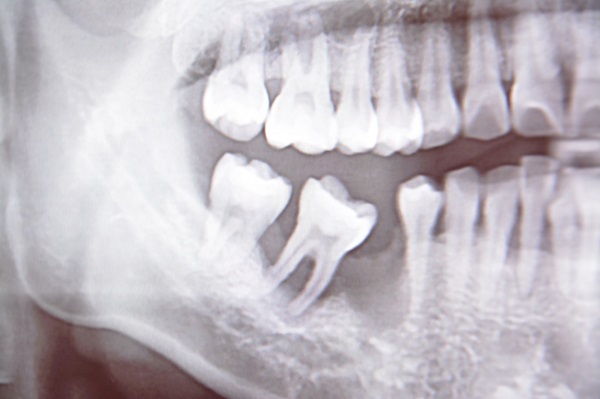

看過口腔缺牙X光照超植的吳醫師很委婉的跟我們說

若爸爸再不做修補未來免不了可能要做全口植牙

口腔裡面剩下了恆齒越來越少

對於飲食咬合會有很大的影響